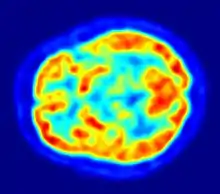

Through positron emission tomography (PET) scans, researchers have established a positive association between increased mental activity and glucose metabolism (Benton & Nabb, 2003). Within minutes of eating, blood-glucose is metabolised in areas of the brain specifically used for higher-cognitive tasks. Thus, cognitive tasks deplete energy; with more difficult tasks placing greater metabolic-demand on the brain. Perhaps not surprisingly then, glucose consumption can improve cognitive functioning. Glucose demonstrates an inverted-U shape effect on cognitive functioning, with 25g being the optimal dosage to improve memory in adults (Owen & Sunram-Lea, 2011). Most pronounced gains appear in tasks of verbal declarative memory (i.e. those involving high cognitive demand), which involve hippocampal brain regions (Owen & Sunram-Lea, 2011). While glucose-rich carbohydrates provide short-term energy-boost, the accompanying release of insulin results in a lowering of blood glucose. Low blood glucose has been linked to changes in relative mood, and a tendency to become irritable and aggressive (Benton, 2002).

The energy needed for self-regulation and self-control comes by way of glucose in the bloodstream (DeWall et al., 2011). As we have already seen, glucose provides a vital source of energy to the brain and is therefore imperative to all cognitive processes. Numerous studies have found that blood glucose levels affect a persons' ability to maintain self-control (Denson et al., 2012; DeWall et al., 2011b; Gailliot & Baumeister, 2007). Moreover, low blood glucose concentration has been associated with poorer attention, difficulty regulating emotions, and even increases in violent and criminal behaviour (Bushman et al., 2014; DeWall et al., 2011b). Interestingly, glucose metabolism becomes less efficient throughout the day (as seen in Figure 2.). This decline in blood glucose concentration has been linked with poorer mood and higher rates of aggression in the evening (Bushman et al., 2014). Due to the cognitive process involved, self-control is thought to be metabolically expensive. That is, it requires a significant amount of energy, which is provided by blood glucose. Understanding this can help to explain ego depletion theory and why self-control is a finite resource.